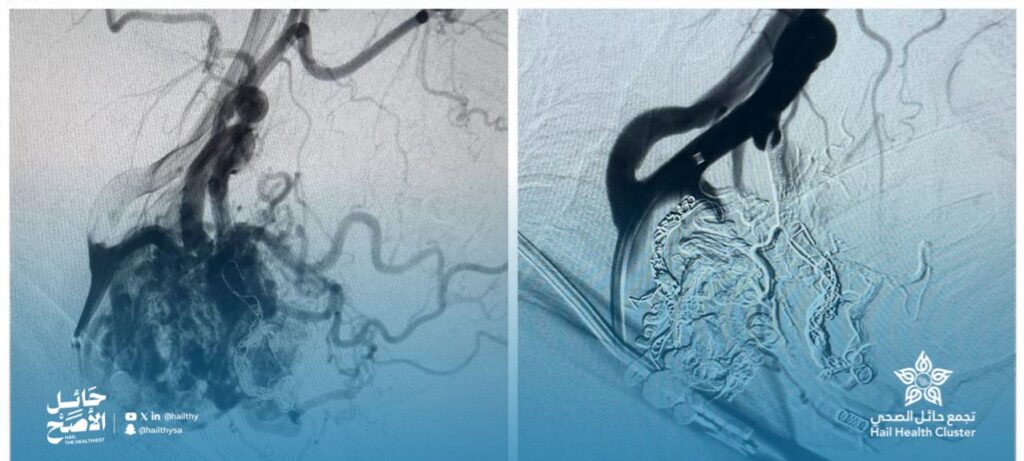

نجح فريق الأشعة التداخلية العصبية في مستشفى الملك سلمان التخصصي في تشخيص وعلاج حالة نادرة من التشوهات الشريانية في منطقتَي الوجه والعنق لدى إحدى المريضات، والتي كانت تعاني من انتفاخات واضحة وطنين مستمر في الأذن نتيجة اضطراب في تدفّق الدم داخل الأوعية وقد تم علاج الحالة باستخدام القسطرة العصبية التداخلية دون الحاجة للتدخل الجراحي، وبكفاءة عالية ويدون مضاعفات، حيث لوحظ تحسن ملحوظ بعد الإجراء، تمثّل في اختفاء الطنين وتراجع الانتفاخ.

ويعكس هذا الإنجاز الدور المتقدم للأشعة التداخلية العصبية في علاج التشوهات الوعائية المعقدة بطرق آمنة وطفيفة التوغل تسهم في تقليل المخاطر وتسريع التعافي وتجنب الجراحة المفتوحة.